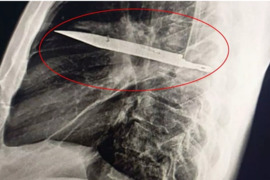

Tanzaniyada kişi xəbəri olmadan səkkiz il sinəsində bıçaqla yaşayıb

Tanzaniyada kişi səkkiz il sinəsində bıçaqla yaşayıb və ancaq tibbi müayinə zamanı bundan xəbər tutub. xəbər verir ki, bu barədə "Mirror" məlumat yayıb. Qeyd olunub ki, Muhimbili Milli Xəstəxanasının həkimləri qeyri-adi halla qarşılaşıblar. 44 yaşlı kişi döş qəfəsində irinin olması şikayət